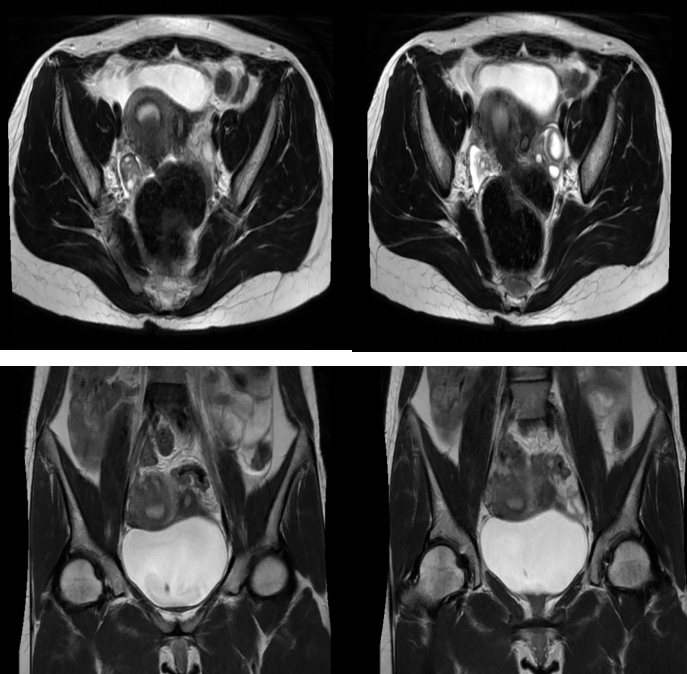

2、2023-07-11MRI示:1、子宫左侧壁异常包块,考虑子宫副腔畸形可能性大,请结合临床。2、左侧卵巢黄体囊肿;宫颈纳氏囊肿。3、盆腔少许积液。4、盆腔内未见明显肿大淋巴结。